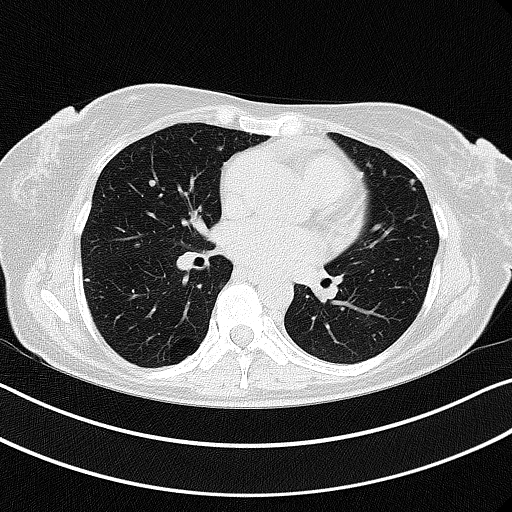

Original NATIVE CT scan (input)

Full window (WL 1023.5, WW 4095 β†’ Low βˆ’1024, High +3071)

Actual HU range: [-1024.0, 2097.0]

Lung window (WL -600, WW 1500 β†’ Low βˆ’1350, High +150)

Actual HU range: [-1024.0, 150.0]

Mediastinum window (WL 40, WW 400 β†’ Low βˆ’160, High +240)

Actual HU range: [-160.0, 240.0]